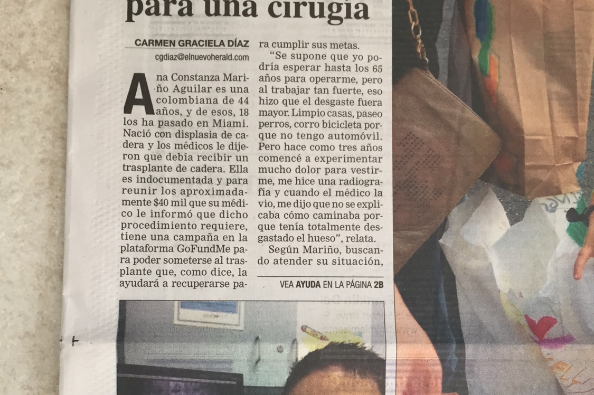

Les comparto fotos de varios medios de comunicación que muy gentilmente me han apoyado UNIVISION,MUNDO FOX,RCN,NTN24,NUEVO HERALD,DIARIO DE LAS AMERICAS.

Les comparto fotos de varios medios de comunicación que muy gentilmente me han apoyado UNIVISION,MUNDO FOX,RCN,NTN24,NUEVO HERALD,DIARIO DE LAS AMERICAS.